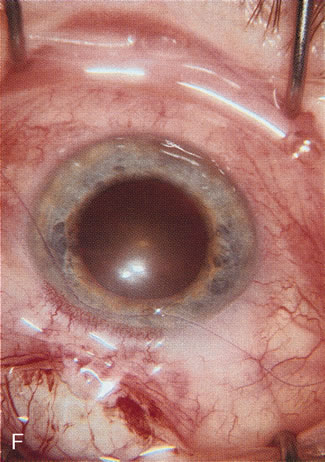

Fig. 1. The anatomic advantage of small incision cataract surgery for the glaucoma patient. A. Long-term bleb function with a large cataract incision is difficult to achieve with either ECCE-trabeculectomy or trabeculectomy followed later by ECCE. This bleb failed to form sufficiently when combined with large incision ECCE. The inflammation, bleeding, and long-term wound healing with stimulation of fibroblasts associated with this technique are more likely to cause bleb failure. In addition, the increased iris manipulation necessary to deliver the nucleus and subsequent iris repair adds to the long-term breakdown of the blood aqueous barrier. B and C. Two-site phacotrabeculectomy has the advantage of small incision cataract surgery combined with separate site trabeculectomy. The incision size is one third the size of the standard ECCE. The inflammation is less severe, and cataract wound healing is confined to the temporal area. Visual rehabilitation with phacoemulsification and foldable IOL is much faster. Phacoemulsification allows successful lens extraction even in the unfriendly environment of a smaller pupil compared with ECCE. The trabeculectomy is performed in an entirely different site, well away from the wound healing associated with temporal phacoemulsification. The likelihood of this filter functioning long-term is greater than with ECCE-trabeculectomy. D. The surgeon also has the option of single-site phacotrabeculectomy with foldable IOL. Both the lens extraction and trabeculectomy are performed through one small 3.5-mm limbal incision.

Fig. 3. Partial bleb failure following clear corneal phacoemulsification with foldable IOL. A. Preoperative bleb appearance prior to temporal lens extraction. Preoperative IOP was 12 mm Hg on no antiglaucoma medications. Time from 5-FU trabeculectomy surgery to lens extraction was one year. B. Bleb appearance 2 months after clear corneal cataract surgery with topical anesthesia. Following lens extraction, increased vascularity was noted along with decreased size of the filtering bleb. IOP increased to 20 mm Hg as early as 2 weeks after surgery, necessitating topical antiglaucoma therapy. C. High magnification view of bleb before lens extraction demonstrates diffuse pale bleb. D. High magnification view of bleb 2 months after surgery. There are vessels surrounding the nasal side of the bleb and the overall bleb size is smaller.

A patient with long-standing primary open-angle glaucoma with a successful glaucoma filtration procedure and IOP of 10 mm Hg on no antiglaucoma medications develops a significant, moderately dense nuclear sclerotic cataract. This patient is best served by small incision cataract extraction with foldable IOL implantation. Less desirable options include ECCE with IOL implant via clear cornea, temporal limbus, or inferior approach. Astigmatism, wound instability, prolonged visual recovery, visual fluctuation, exposed sutures, and bleb failure are the major drawbacks to large-incision lens extraction. Even after the surgeon has mastered large-incision clear corneal cataract extraction, long-term wound shift and astigmatism are a chronic problem (Fig. 6). Inferior cataract extraction is difficult for those not experienced with it. With the advent of small-incision phacoemulsification surgery, the surgeon is now able to use a limbus approach adjacent to the bleb or a clear corneal temporal approach. Postoperative inflammation is less with the smaller incision, and filtering blebs are more likely to survive. Patients with IOP greater than 10 mm Hg after a filtering procedure are more likely to experience permanent IOP elevation after phacoemulsification. Patients should understand that IOP elevation post cataract extraction is always an issue, even with a functioning filter.

Fig. 6. ECCE following trabeculectomy. The larger corneal incision associated with ECCE leads to a host of problems that are typically less severe with small incision cataract surgery. With improved phacoemulsification techniques, this type of incision is infrequently encountered. This bleb failed following ECCE, and topical antiglaucoma therapy was restarted. Long-term wound drift; astigmatism, and corneal decompensation are additional visual factors. However, when the nucleus is brunescent and phacoemulsification risky, surgeons with the skill to convert to ECCE through a clear corneal incision are at a significant advantage. This 11-mm free hand incision takes considerable practice and skill to master.